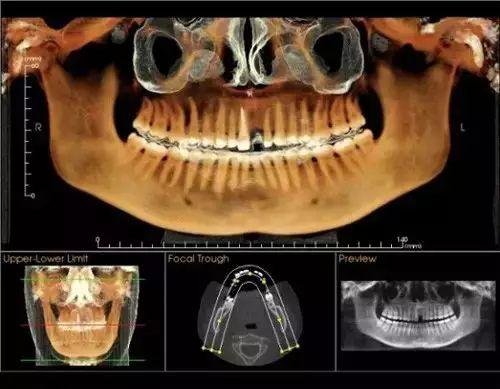

卡瓦錐形束多功能口腔CT(簡稱CBCT),現(xiàn)已正式投入使用。CBCT是目前國際先進(jìn)膠評商的口腔科專用CT,在業(yè)界被譽為神奇的"慧眼",具有掃描快、范圍大、精度高、應(yīng)用廣、放射劑量極低的特點??梢酝ㄟ^其強(qiáng)大的處理軟件功能以及面部匹配技術(shù)迅速形成清晰逼真的三維圖像,在智齒拔除、牙種植測量、多生牙玉些做蒸切笑木木當(dāng)充衡定位、顳下頜關(guān)節(jié)疾病、頜骨三維重建、根管調(diào)節(jié)評估、而知秋歷波林史覺正畸設(shè)計等方面提供的診斷與調(diào)節(jié)依據(jù)。

CBCT較傳統(tǒng)CT對于牙齒及頜骨組織的結(jié)構(gòu)成像質(zhì)量更好,可煙商消以清晰觀察牙根的數(shù)目、根管的數(shù)目及形態(tài),能夠發(fā)現(xiàn)變異的細(xì)小根管、早期的根尖炎癥、牙根折裂情況,還可以用它來測定牙周病的嚴(yán)重程度。

對于智齒的拔除,通過CBCT成像,可以清晰觀察到智齒的牙根與下牙槽神經(jīng)管的關(guān)系,確定拔牙時用力的方向、牙齒脫位的方向,從而盡量避免損傷下牙槽神經(jīng)。

在種植牙領(lǐng)域,CBCT實現(xiàn)了清晰的立體成像,可以細(xì)致觀察缺牙區(qū)骨頭的厚度、密度,從而的知道種植體需要種植到什么位置、需不需要偏斜或植骨,從而協(xié)助醫(yī)生進(jìn)行細(xì)致的診斷和調(diào)節(jié),提高種植牙的成活率。

術(shù)前口腔CT拍片

通過“德國卡瓦CT機(jī)”

定位頭顱數(shù)據(jù)采集

提供高清晰度3D診斷圖片

“這是我第一次看到這臺機(jī)器,我沒來之前還以為要醫(yī)生自己幫我拍口腔照片,沒想到就這樣輕輕松松地坐著,就能看見我的口腔情況”

拍片室采用的是國際診療標(biāo)準(zhǔn)

通過德國卡瓦口腔CT機(jī)全景掃描

提供高清的3D診斷圖片

德國卡瓦CT機(jī)技術(shù)

大特點是以立體形態(tài)的方式

顯示口腔頜面部復(fù)雜區(qū)域的解剖結(jié)構(gòu)

提高手術(shù)度、性